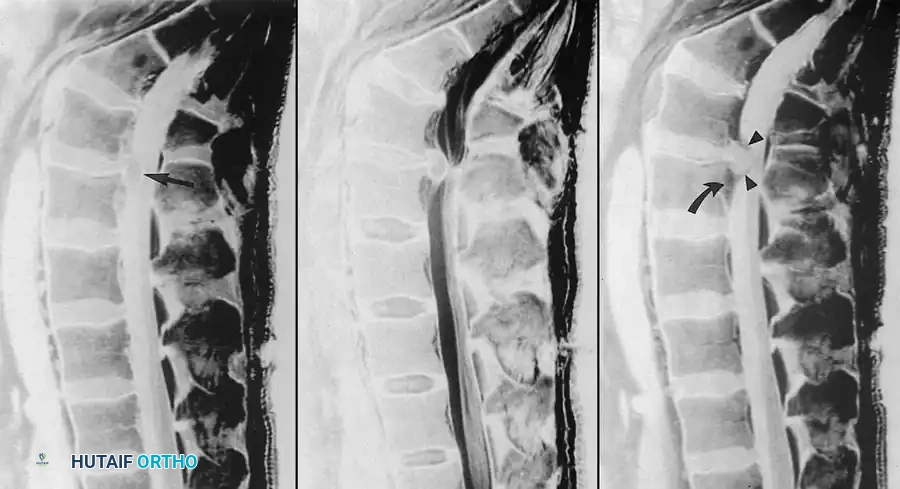

Fig. 2-26 Recurrent lumbar disc extrusion (herniation). A, Sagittal T1-weighted image shows intermediate signal intensity in L4-5 disc material (arrow) surrounded by hypointense cerebrospinal fluid. B, Sagittal T2-weighted image shows displaced disc material contiguous with intervertebral disc. Hyperintense cerebrospinal fluid provides improved contrast. C, Sagittal T1-weighted image after gadolinium administration shows enhancement of epidural venous plexus (curved arrow) and overlying granulation tissue (arrowheads), but no enhancement of disc material.

After intravenous gadolinium administration, repeat T1-weighted images typically demonstrate robust enhancement of vascularized scar tissue or epidural fibrosis. Conversely, beyond the immediate postoperative period, avascular disc material does not enhance.

Before the advent of intravenous gadolinium contrast agents, making a definitive distinction between recurrent disc material and postoperative epidural scar tissue (fibrosis) was nearly impossible with CT myelography or non-contrast MRI. The introduction of gadolinium has revolutionized the postoperative evaluation of the spine.